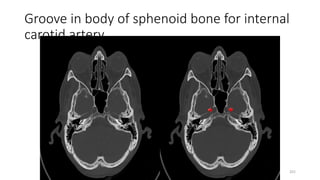

LEVEL-9

Groove in body of sphenoid bone for internal

carotid artery